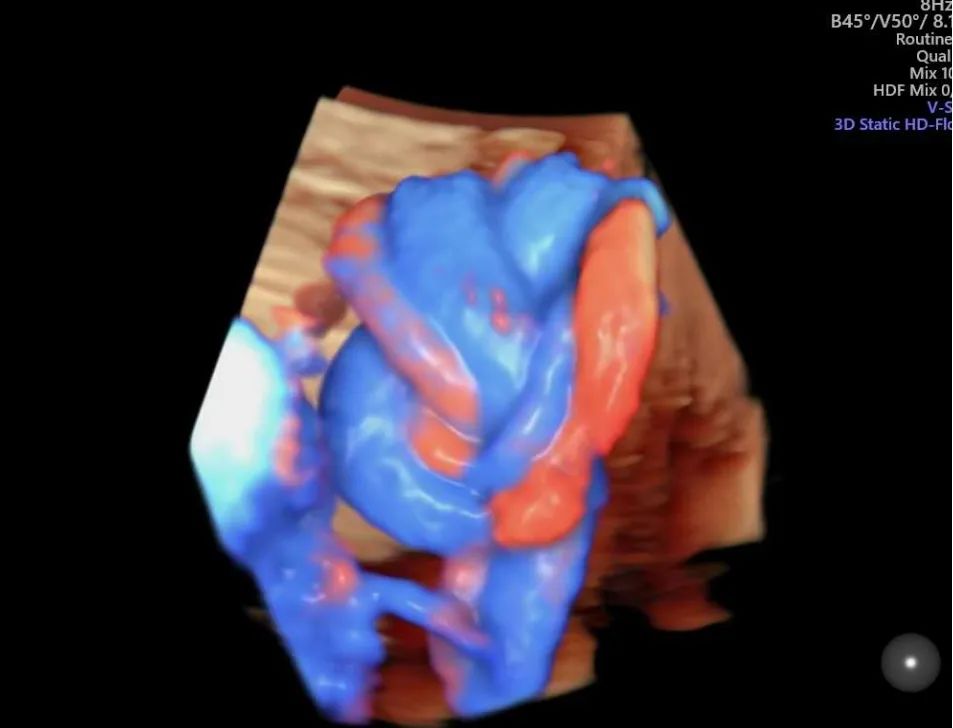

完全性肺静脉异位引流

XXX 女 48 岁 G1PO 孕 29W1D 既往无不良孕史

外院系统、四维超声未发现心脏显著异常,心脏超声检查时发现左心系统小,瓣环及主动脉峡部略细,肺静脉异位引流待排。为进一步明确诊断,特来我院请张军教授会诊。我科行胎心检查时发现左房内未见肺静脉开口;四只肺静脉在左房后方形成共同静脉干后向下走形进入肝静脉。遂做出完全性肺静脉异位引流(心下型)的诊断,为了解生后手术情况,患者到上级医院会诊,证实了此诊断。

正常情况下,四支肺静脉均应引流入左心房。完全性肺静脉异位引流指四条肺静脉形成共同肺静脉干,未引流入左心房,而通过不同途径引流入右心房,右心房内的动静脉混合血一部分经三尖瓣入右心室、肺动脉,一部分经房间隔缺损引流入左心房供应体循环。

TAPVC 发病率低、畸形复杂,诊断相对困难。因存在大量右向左分流,所以新生儿期即出现紫绀、呼吸困难等缺氧症状,情况危急,需早期手术。如果在产前能做出明确诊断,有利于生后做好相应处理措施。